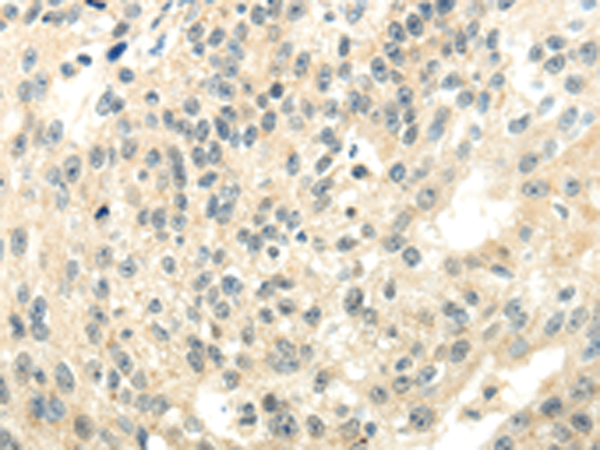

分类: 科研抗体货号: P10678别名:应用: WB,IHC反应种属: Human, Mouse, Rat